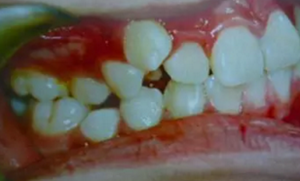

牙齒需要矯治的患者,往往牙齒和排列和咬合關(guān)系多會出現(xiàn)錯亂,那些錯亂的牙齒即使不拔除,它也是沒有功能的,因為它和對頜的牙齒咬不上。

1.png

并且,這些排列不正常的牙齒很難清理干凈,容易在它的周圍存留很多食物殘留,久而久之就形成蛀牙,最后也是一拔了之。我們醫(yī)生拔牙的時候有一定選擇的,一般是拔除那些壞牙、沒有功能的牙。